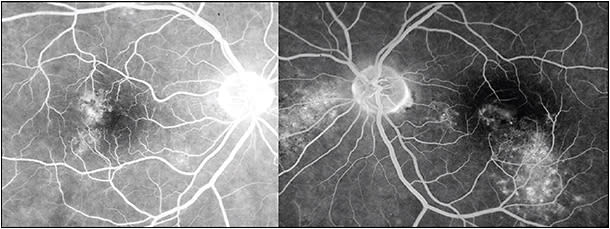

The natural history in the vast majority of CSC cases is spontaneous resolution within 2-3 months (so-called classic CSC). In these cases, central vision is minimally affected and usually returns to normal after reabsorption of the subretinal fluid (Figure 1). However, as many as 10% of all patients with CSC develop persistent serous macular detachment (chronic CSC or “diffuse retinal pigment epitheliopathy” [DRPE], lasting 3 months to 6 months or longer).10 In these DRPE cases, progressive and irreversible visual decline can be associated with the development of central RPE atrophy and (due to increased diffusion distance between the oxygenating and nourishing choriocapillaris, trophic RPE, and the photoreceptors) cystoid macular degeneration and foveal atrophy (Figures 2 and 3).11-15

Also, persistent subretinal fluid in a patient with CSC may be associated with the development of choroidal neovascularization (CNV) or polypoidal choroidal vasculopathy (PCV; which is also associated with pachychoroid) in these patients.27 Also, the appearance of subretinal or sub-RPE hemorrhage in a patient diagnosed with CSC would indicate evolution to CNV or PCV (Figure 4). These developments would necessitate a different treatment approach (prompt intravitreal anti-VEGF treatment or combination intravitreal anti-VEGF and photodynamic therapy [PDT]).28,29